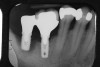

Conventional periodontal therapy should be instituted if inflammation develops around an implant. Therapy should include efforts to improve patient oral hygiene, using similar methods as around natural teeth (Figure 4A and Figure 4B). Lang et al suggested a novel, systematic stepwise approach for the prevention and treatment of peri-implant diseases referred to as the cumulative interceptive supportive therapy (CIST) protocol46 (Table 4). This system is based on periodic monitoring with implementation of treatment as thresholds for a particular condition are met. The first step is protocol A, then B and, if conditions continue to worsen, the case may require more advanced treatment, which may include comanagement with a specialist who has implant training to execute protocol C, and finally D.20 Protocol A is used to control inflammation in peri-implant mucositis, that is, implants with minimal increase in pocket depth, slight (+) bleeding on probing, marginal erythema, plaque, and/or calculus. The therapeutic endpoint is to resolve inflammation with cautious mechanical debridement (using plastic curettes and rubber cup prophylaxis), twice-daily swabbing with 0.12% chlorhexidine, and a review of home care and patient motivation. Protocol B is initiated for conditions that exhibit similar mucositis features but with deeper pocket depths (4 mm to 5 mm); however, there is still no loss of supporting bone. The treatment should include the therapies of protocol (A), plus locally delivered antibiotic (minocycline microspheres, doxycycline gel) at the infected implant site(s). Recent studies have shown the use of minocycline microspheres may be beneficial in treatment of peri-implant mucositis and peri-implantitis.46 Management of early peri-implantitis, protocol C, requires a more robust approach and is used in conditions with evidence of osseointegrated bone loss of < 2 mm and pocket depths > 5 mm. The strategy should comprise the modalities for protocols A and B with the addition of systemic antibiotic therapy (metronidazole 250 mg t.i.d. for 7 days or amoxicillin 500 mg t.i.d. for 10 days).

Figure 4a  Use of a proxi-brush and large-diameter floss to perform plaque control around an implant-supported/retained prosthesis

Figure 4a

Figure 4b  Use of a proxi-brush and large-diameter floss to perform plaque control around an implant-supported/retained prosthesis

Figure 4b